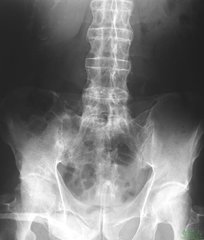

强直性脊柱炎是种常见的风湿免疫性疾病,主要因脊柱发生病变而导致的慢性疾病,而且,处于不同时期的强直性脊柱炎患者,所受到的伤害也是不同的,症状也是不同的,这就要求我们辨病病症进行治疗。临床资料显示,强直性脊柱炎疾病在早期是完全能够治疗的,当疾病发展到中晚期,采取有效的治疗,能达到控制病情,保护受累关节,恢复关节功能的目的。

需要注意的是,与其它疾病一样,如果在早期进行治疗,强直性脊柱炎患者是可以治疗的,而且治疗后的患者与正常人没什么区别。到了中晚期脊柱骨桥形成,通过治疗只能达到疼痛症状消失,骨骼变形停止,病情不发展的程度,这就是医生说的临床治疗。强直性脊柱炎中晚期脊柱骨桥形成,根本不能通过治疗使骨桥消失达到早期那样的临床治疗效果。如果强直性脊柱炎中晚期患者治疗后,想达到骨质彻底治好,这样就走了治疗强直性脊柱炎思想上的误区,强直性脊柱炎患者是永远达不到治好的目的的。>>>强直性脊椎炎不治疗会产生哪些危害?点击免费咨询医生